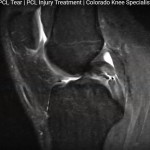

MRI in Medial Meniscal Tear

Courtesy: Robert LaPrade MD, Complex Knee Surgeon Steadman-Philippon Clinic, Vail, Colarado, USA http://drrobertlaprademd.com/ Address: 181 W Meadow Dr #400, Vail, CO 81657, USA